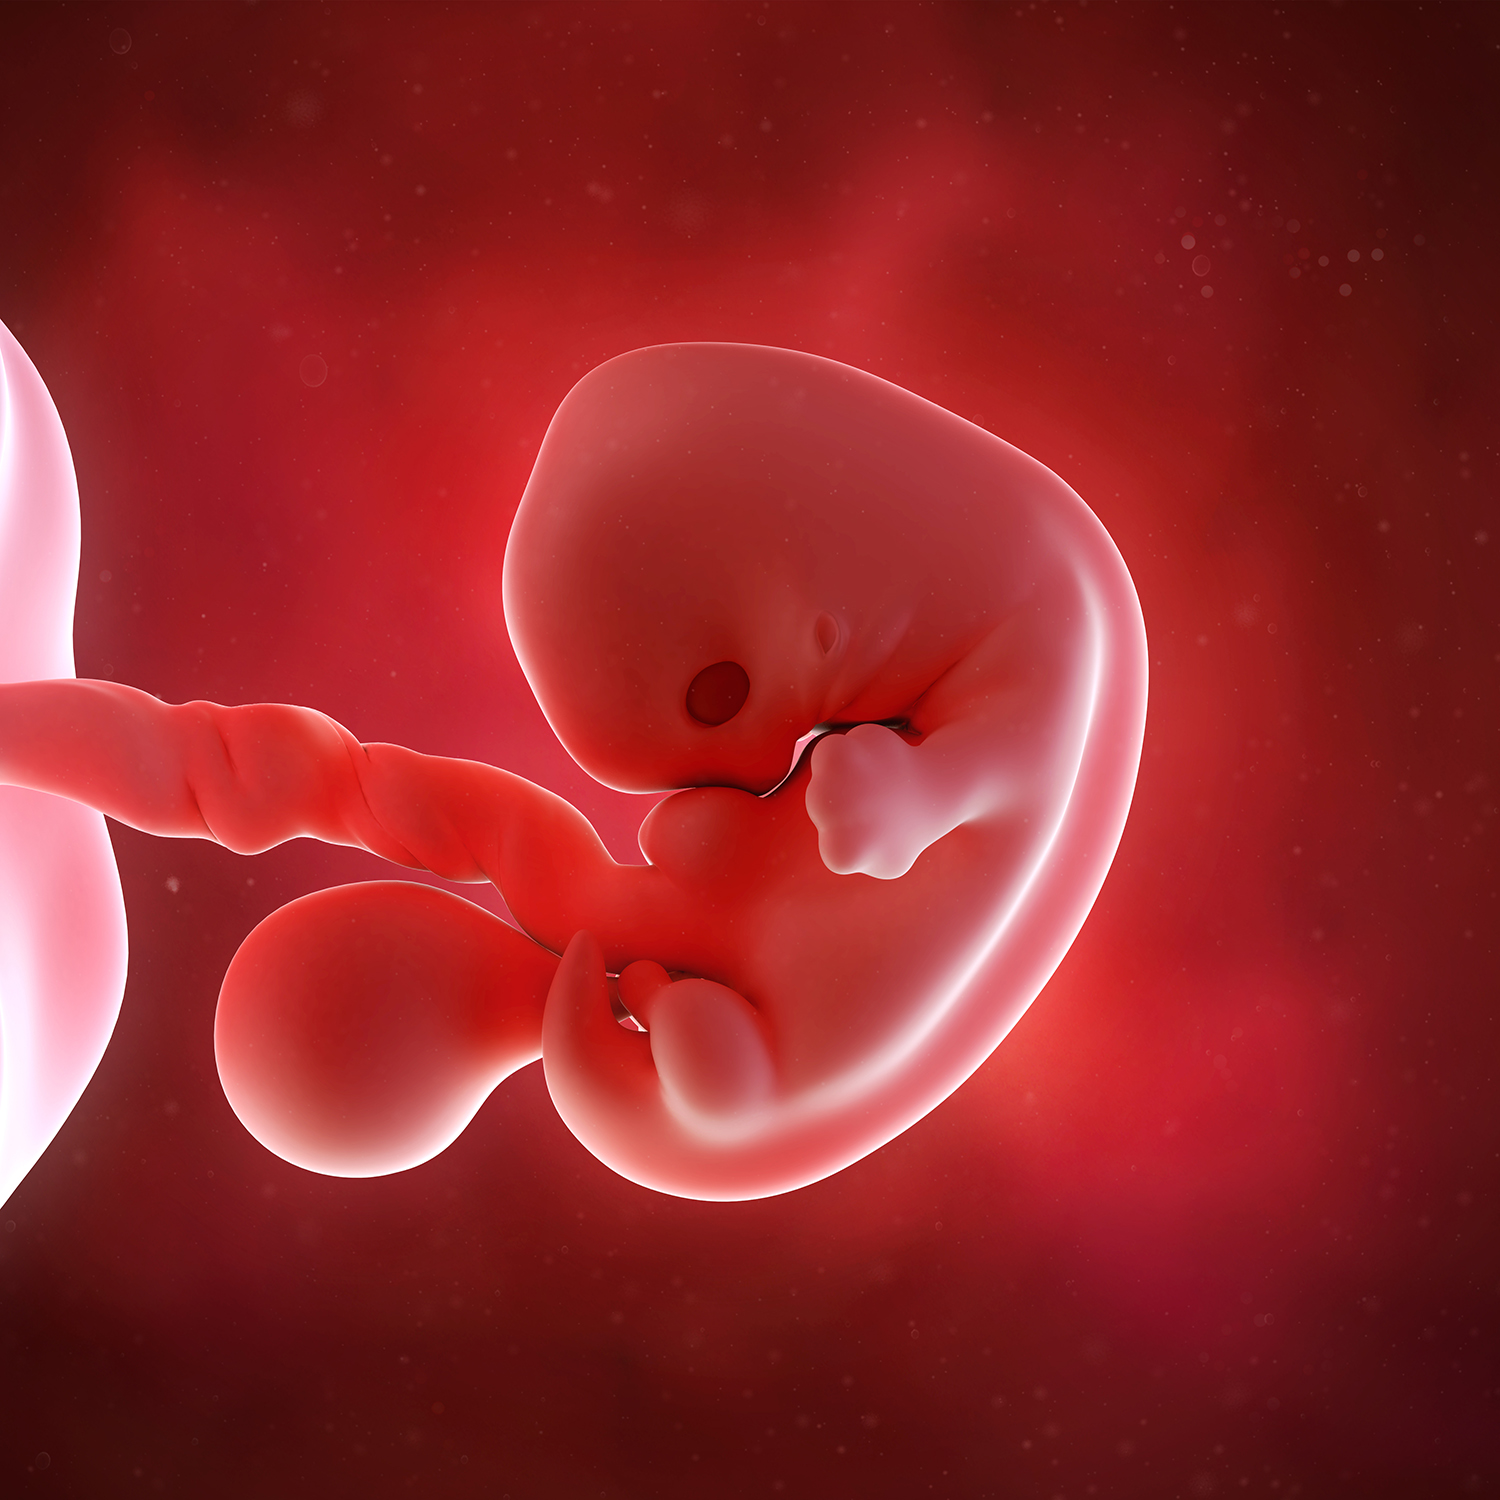

Understanding Your Baby’s Development in Week 3

3 Weeks Pregnant – Pregnancy Week-by-Week

Second Trimester Fetal Development: Images of Your Growing Baby | Parents